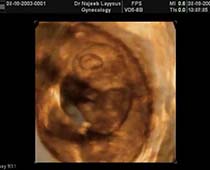

- Hysteroscopy Photos